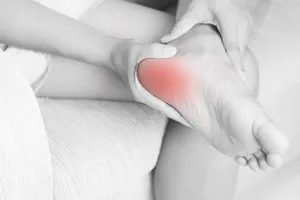

· 뒤꿈치 통증

1. 족저근막염

발바닥 아치를 지지하는 족저근막에 반복적인 스트레스가 가해져 발생하는 가장 흔한 원인입니다. 아침에 첫발을 디딜 때 심한 통증이 느껴지는 것이 특징입니다. 과도한 운동, 평발, 고령 등이 원인이 될 수 있습니다. 휴식, 냉찜질, 스트레칭, 맞춤 깔창, 체외충격파 치료, 스테로이드 주사 등이 있습니다. 심한 경우 수술이 필요할 수 있습니다.